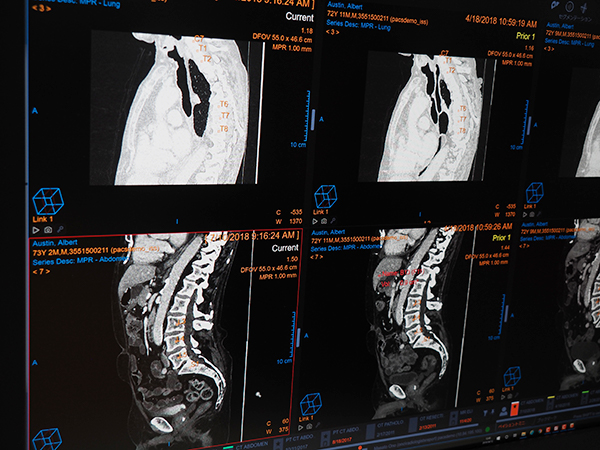

展示では,“Clinical Collaboration Platform”として医用画像情報システム「Vue PACS」や放射線情報システム「CARESTREAM RIS-J」の新機能を中心に紹介した。今年のITEMのトピックスともいえるAIへの取り組みとしては,RSNA2018でも紹介されたゼブラ・メディカル・ビジョン(ゼブラ社)のAIエンジンのVuePACSへの統合,自社開発の病変管理機能(リージョンマネジメント)やCTのspine自動ラベリングなどを紹介した(すべてW.I.P.)。画像データをサーバに登録した段階でAIによるスクリーニング終了しており,ワークリストオーケストレーターのワークリスト上には優先順位などをつけて表示される。

自社開発のAIとしてspine Labelingの自動化機能を紹介